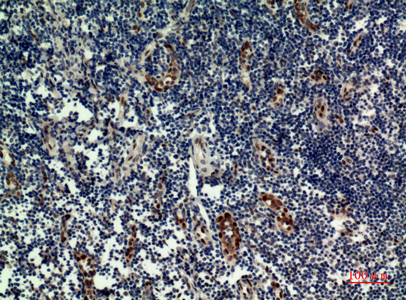

WB,IHC-P,IF-P,IF-F,ICC/IF,ELISA

稀释比(Dilution Ratio)

WB 1:500-1:2000, IHC-P 1:100-1:300, ELISA 1:20000, IF-P/IF-F/ICC/IF 1:50-200